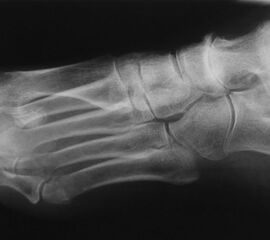

Talonavikular-, navikulocuneiforme- und calcaneocuboidale Arthrosen, also Arthrosen in der Chopart- und Bona-Jäger-Gelenklinie, zeigen sich wesentlich seltener und können in Kombination von Arthrosen aller Gelenke des Mittelfußes auftreten. Die Diagnostik beinhaltet grundsätzlich die ausführliche Untersuchung des gesamten Fußes im Stehen, im Liegen und beim Gehen. Ein Röntgenbild des Fußes im Stehen in zwei Ebenen, ergänzend eine schräge Aufnahme, sowie Saltzman und OSG-Bildgebung sind für die Diagnose und Therapieplanung essentiell. Bei Planung eines operativen Eingriffes sollte eine Computertomographie des gesamten Fußes durchgeführt werden. Zunächst sollte die konservative Therapie mittels Schmerzmedikation, Infiltration, Manueller Therapie, Einlagen, Schuh-Modifikation, Orthesen, orthopädischem Schuhwerk und ggf. eine Strahlentherapie voll ausgeschöpft werden. In zweiter Linie steht die operative Therapie. Chirurgische Eingriffe beinhalten typischer Weise die selektiven Arthrodesen der betroffenen Mittelfußgelenke. Hier wird meist die mediale Säule behandelt, die Arthrodesen der mobileren lateralen Säule sind ein Thema in der Diskussion 2.

Die Diagnostik beinhaltet die komplette klinische Untersuchung des Patienten bei entkleidetem Unterkörper mit Funktionstests, Abtasten der entsprechenden Gelenkreihen (Chopart, Bona Jäger und Lisfranc) und Überprüfung der Beweglichkeit der Tarsometatarsalgelenke mit dem Klaviertasten-Test 11. Beurteilt werden Fußformveränderungen, osteophytäre Anbauten, sowie eine mögliche Verkürzung des M. gastrocnemius-soleus-Komplexes mit Hilfe des Silfverskjöld-Tests 12. Es werdemRöntgenaufnahmen des Fußes im Stehen in 2 Ebenen und ergänzend eine Schrägaufnahme des Fußes durchgeführt. Bei Fußfehlstellungen erfolgt zusätzlich das Röntgen des oberen Sprunggelenks im Stehen und eine Saltzman-Aufnahme 13.